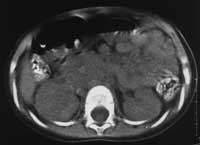

Рис. 4. Нейробластома правого надпочечника у б-го С., 1,5 лет.

(б) КТА. НПВ компремирована, располагается в толще опухоли. Сброс венозной крови в полунепарную вену. Деформация и отклонение правой почечной артерии.